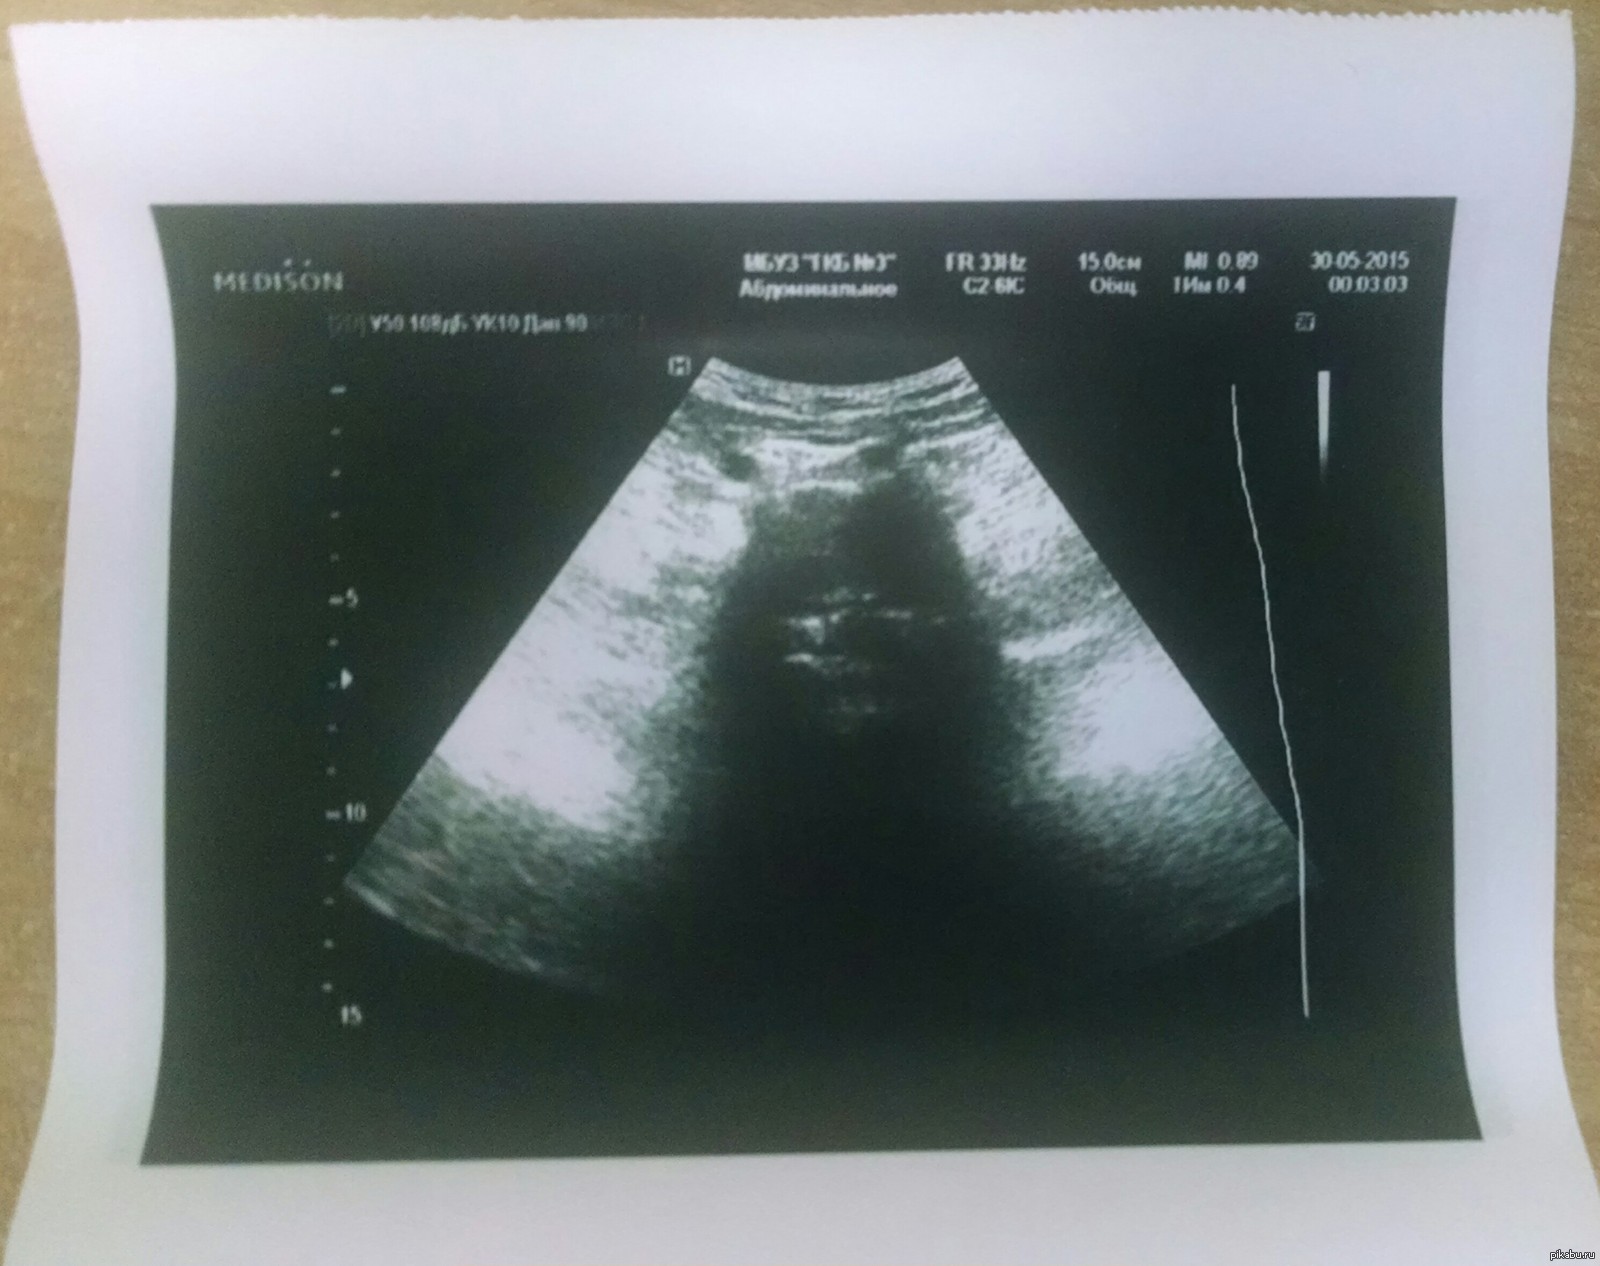

DrDave 10 лет назад У вас будет Дарт Вейдер!) Интересное абдоминальное УЗИ получилось) Фотал на Motorola Droid Maxx [моё] УЗИ Дарт Вейдер Star Wars